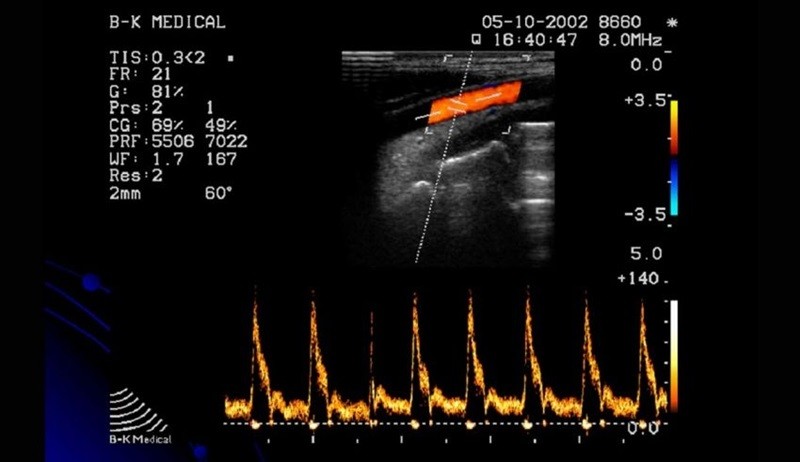

Siêu âm Doppler là một kỹ thuật chẩn đoán y khoa sử dụng sóng siêu âm để đánh giá lưu lượng máu trong mạch máu, bao gồm cả động mạch và tĩnh mạch. Dựa trên hiệu ứng Doppler, kỹ thuật này đo lường sự thay đổi tần số của sóng siêu âm phản xạ từ các tế bào máu đang chuyển động. Siêu âm Doppler có thể hiển thị thông tin quan trọng về tốc độ và hướng của dòng máu, giúp phát hiện các vấn đề như tắc nghẽn mạch máu, động mạch bị thu hẹp hoặc cục máu đông.

Có một số loại siêu âm Doppler, bao gồm Doppler màu (hiển thị lưu lượng máu theo mã màu), Doppler liên tục (đo lưu lượng máu tốc độ cao) và Doppler năng lượng (nhạy hơn trong việc phát hiện lưu lượng máu nhỏ). Ứng dụng của siêu âm Doppler rất đa dạng, từ chẩn đoán bệnh lý tim mạch, theo dõi thai kỳ, đến đánh giá lưu lượng máu qua khối u hay sau ghép tạng. Đây là phương pháp không xâm lấn, an toàn, hiệu quả và được ứng dụng rộng rãi trong y học hiện đại.

Hình ảnh siêu âm Doppler màu